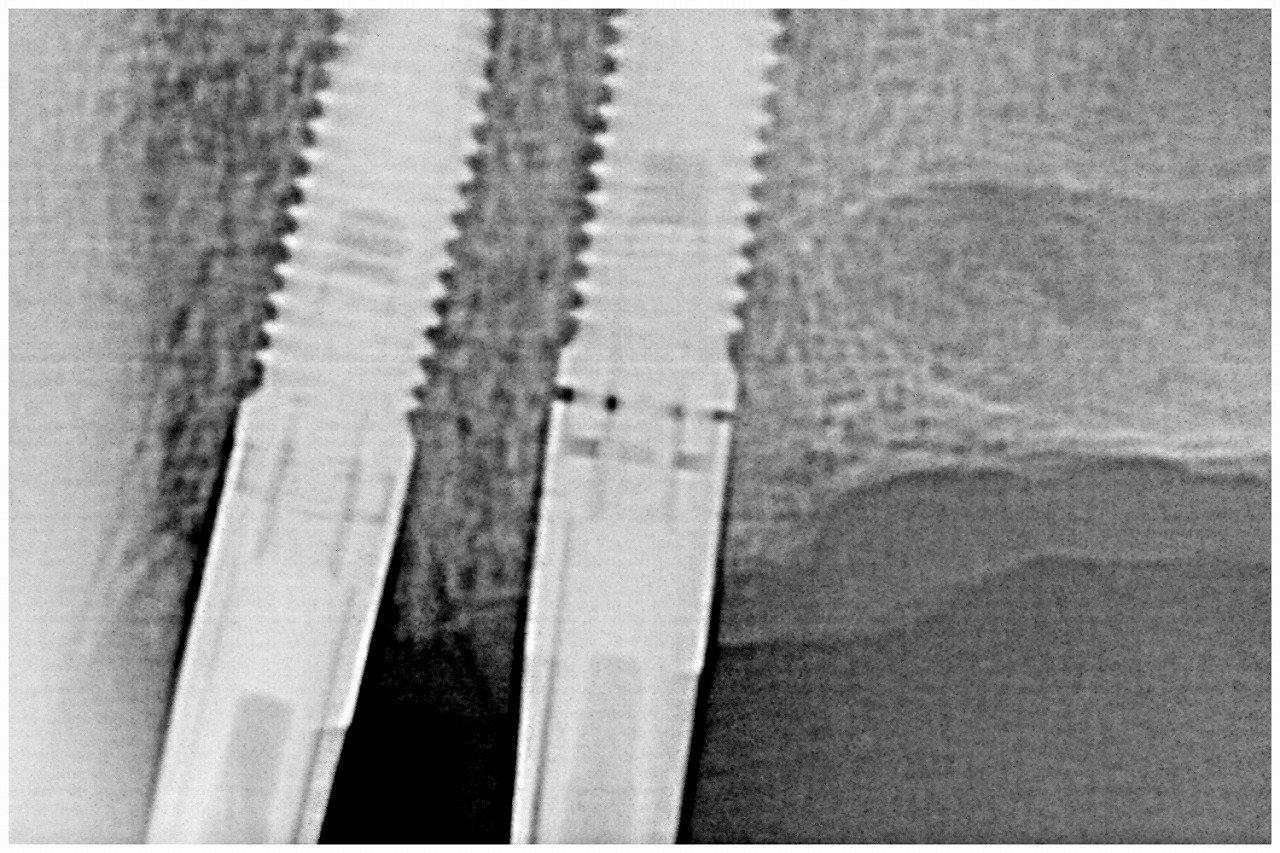

深埋めなので骨と当たっています 確認用のデンタルレントゲン